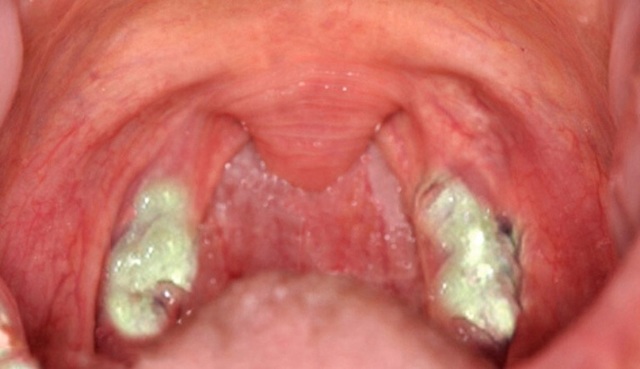

У детей число атипичных клеток возрастает при коклюше, пневмонии, кори, тяжёлых формах гриппа, гнойной ангине, менингите. ![ЛИМФОЦИТЫ В КРОВИ У РЕБЕНКА ПОВЫШЕНЫ: [причины, лечение]](https://dentalcare-rnd.ru/wp-content/uploads/2020/04/da20465f053cdedc03649246e9ca04be.jpg)

У детей атипичные лимфоциты повышаются из-за гнойной ангины